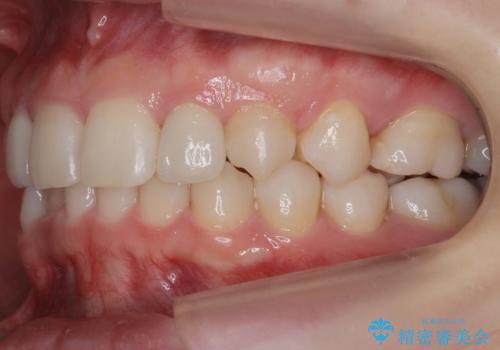

抜歯したスペースを使い、歯並びを整え、さらにその隙間を利用して細い歯を大きく整えてセラミックで被せるという総合的な治療を行いました。

マウスピース矯正→上顎両側2番のセラミック、左下67の虫歯治療 の順で行いました。

矯正治療→ホワイトニング→セラミック の順で行なっています。

ホワイトニングで綺麗に白くした歯に合わせて、被せています。